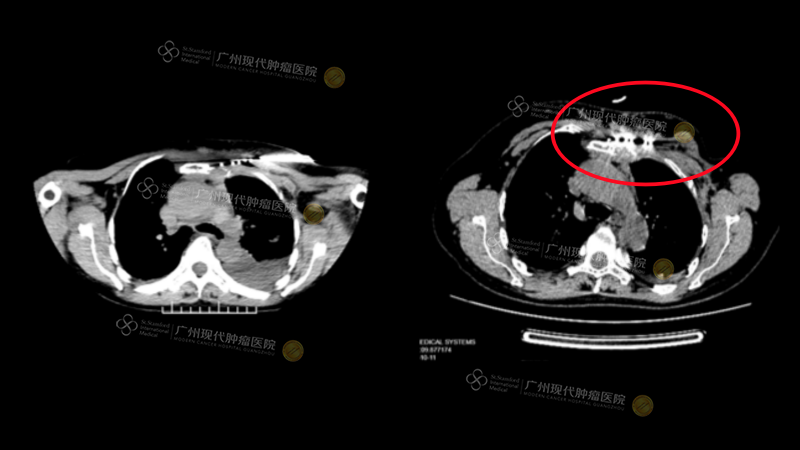

Through a series of typical cases, Professor Wang vividly illustrated the clinical application value of these minimally invasive techniques. One case involved a breast cancer patient with bone metastases whose pre-treatment pain score (NRS) was as high as 10. Even with high doses of conventional painkillers, the relief was insufficient. After multidisciplinary team (MDT) discussion, a CT-guided cryotherapy was performed, resulting in significant pain relief and a marked improvement in the patient’s quality of life.

Another case involved a breast cancer patient with post-operative recurrence and chest wall and bone metastases. This patient also faced unsatisfactory pain relief with conventional medications (NRS 8). After undergoing radioactive seed implantation, the patient’s pain was effectively controlled, and both quality of life and functional status (Karnofsky Score) improved.